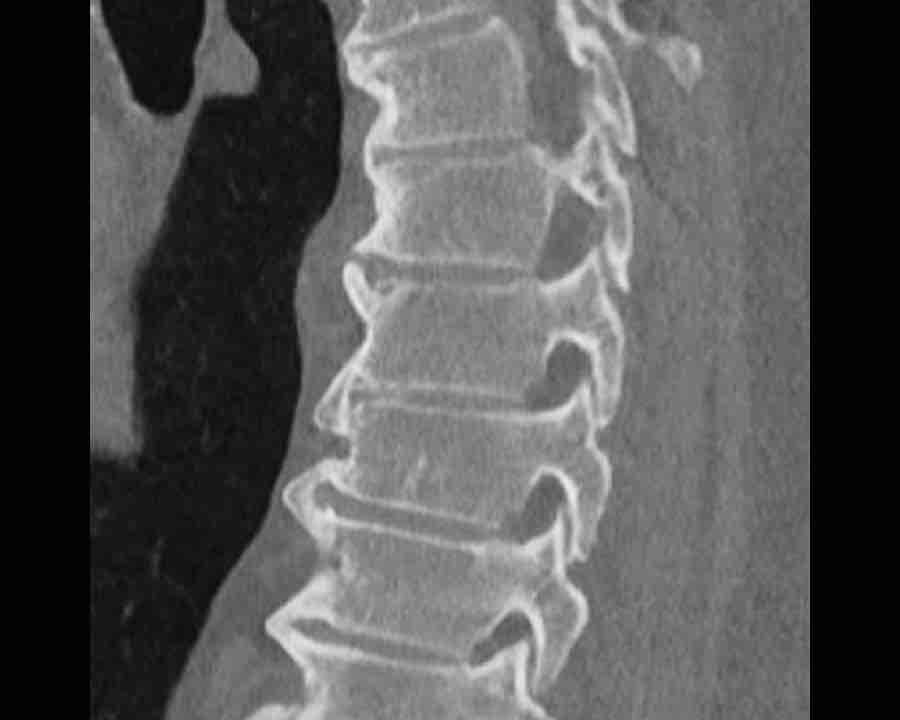

Scroll through images.

What are the findings?

Findings

- C injury? No.

- Signs of a rigid spine?

Yes, a B3 injury is very likely. - A subtle fracture on the anterior vertebral body.

Conclusion

Injury type B3.